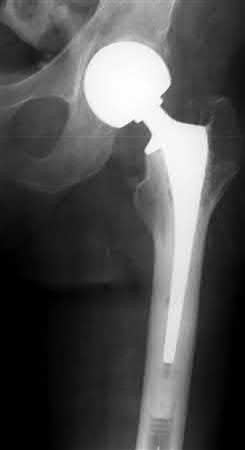

A 64-year-old woman is thrown off a horse, sustaining the injury shown in Figures A and B. She undergoes surgical fixation as seen in Figures C through E. What is the most commonly reported complication of this procedure?

1) Axillary nerve injury

2) Valgus migration of the fracture

3) Nonunion

4) Hardware failure

5) Screw penetration

The patient in the scenario has a 2-part proximal humerus fracture treated with a locking plate as seen in Figures A-E. The most common complication with the use of this implant is screw penetration. The terms screw cut out and penetration are often used interchangeably in the literature with cut out appearing more frequently in reports regarding intertrochanteric fractures.

Owsley et al retrospectively reviewed 53 proximal humerus fractures treated with locking plates and the same post-operative protocol. The most common complication was screw cut out or penetration, followed by varus displacement. They concluded that 3 and 4-part fractures in patients over 60 years have a higher incidence of failure.

Agudelo et al retrospectively reviewed 153 patients at a level-one trauma center treated with proximal humerus locking plates, investigating modes of failure for the implant. They determined that varus malreduction (head-shaft angle